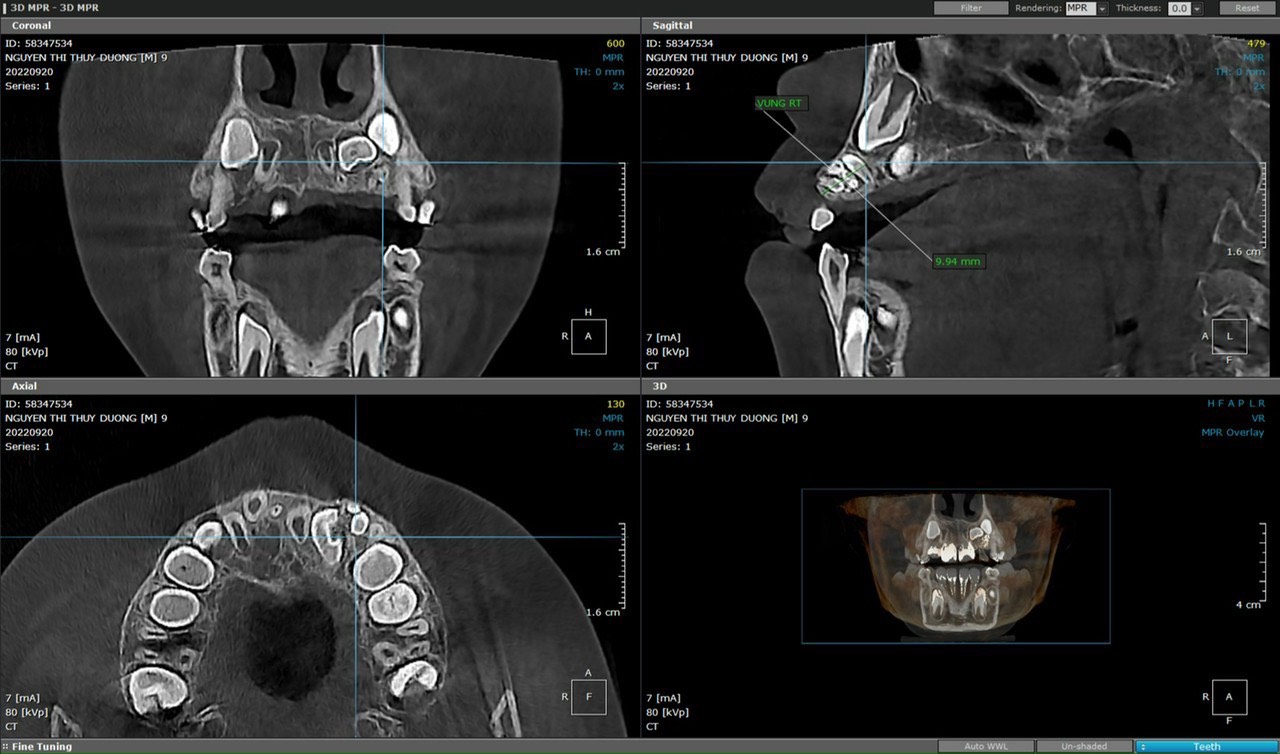

Trường hợp cháu N.T. T.D ( 9 tuổi, địa chỉ ở Minh Đức, Việt Yên) được bố mẹ đưa đến Bệnh viện Đa khoa tỉnh Bắc Giang khám do có răng thừa vùng hàm ếch. Sau khi được bác sĩ thăm khám và chụp X-quang xương hàm, phát hiện một khối u răng tương ứng với vùng răng số 22 và răng thừa vùng hàm ếch ngay sau răng số 11. Người bệnh được chẩn đoán: u răng vùng răng số 22 và được chỉ định phẫu thuật lấy u. Ca phẫu thuật kéo dài 60 phút, đã loại bỏ răng sữa số 2 bên trái, lấy răng thừa, loại bỏ khối u răng. Sau phẫu thuật bệnh nhân ổn định, vết mổ tốt, kiểm tra chụp X-Quang sau phẫu thuật không còn hình ảnh u răng.